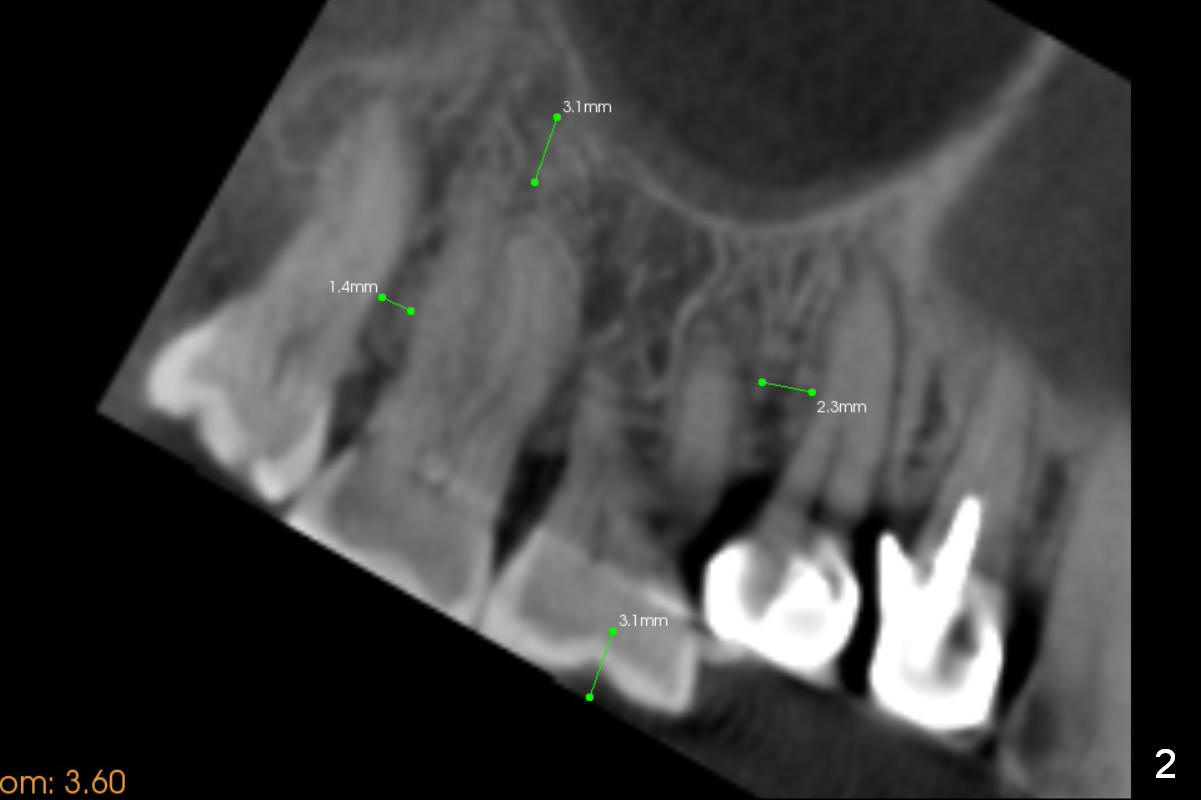

Fig.8 is a preop palatal view of the region. When the segment is lift (Fig.89 arrow), use a twisted wire (lingual retainer; blue line) and composite (red dots) for fixation. The splint may be also used for fixation. On the right, use a thin ortho wire to tighten the splint against mini implants, while on the left, thin ortho wire and composite will be used. The patient will eat soft diet for several months. Keep good oral hygiene.